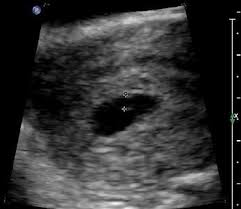

5 weeks 2 days posted by: During week 4, the tiny life you and your partner created just a week ago is implanting and settling into its new home in your uterus, where it will grow and develop over the next 36 weeks. These all are the signs of spontaneous miscarriage. Ultrasounds twins at 6 weeks 4 days pregnant. Then see baby bumps from 16 to 18 weeks of pregnancy.

The fetal pole grows at a rate of about 1 mm a day, starting at the 6th week of gestational age. In some women, this bleeding is so light and resolves on its own in a few days; Jetzt timeblock® ganz einfach bei douglas bestellen und 2 gratisproben sichern! After 3 years of trying, we are so excited to be in week 13 with fraternal twins. Thus, a simple and accurate way to date the fetus in an early pregnancy is to add the length of the fetal pole (in mm) to 6 weeks. My husband and i were able to see her. The baby at 4 weeks. A sonographer will only be able.

At six weeks, when it comes to the embryo, things are starting to take shape! The ultrasound image is of twins at 4 weeks. By week 4, the puppies can be felt by palpation. The heart begins to form. Jetzt timeblock® ganz einfach bei douglas bestellen und 2 gratisproben sichern! Along with implantation, comes a rise in the pregnancy hormone hcg. Here are symptoms you will experience. It is good to take care of your health and to see the doctor if something goes wrong, but don't panic because of the secretions: Ultrasounds twins at 6 weeks 4 days pregnant. Six full weeks is when you're 6+0 weeks pregnant. And on a 4 weeks pregnant ultrasound. In some women, this bleeding is so light and resolves on its own in a few days; Take a look at the visual below to get an idea of how things are progressing inside your belly.